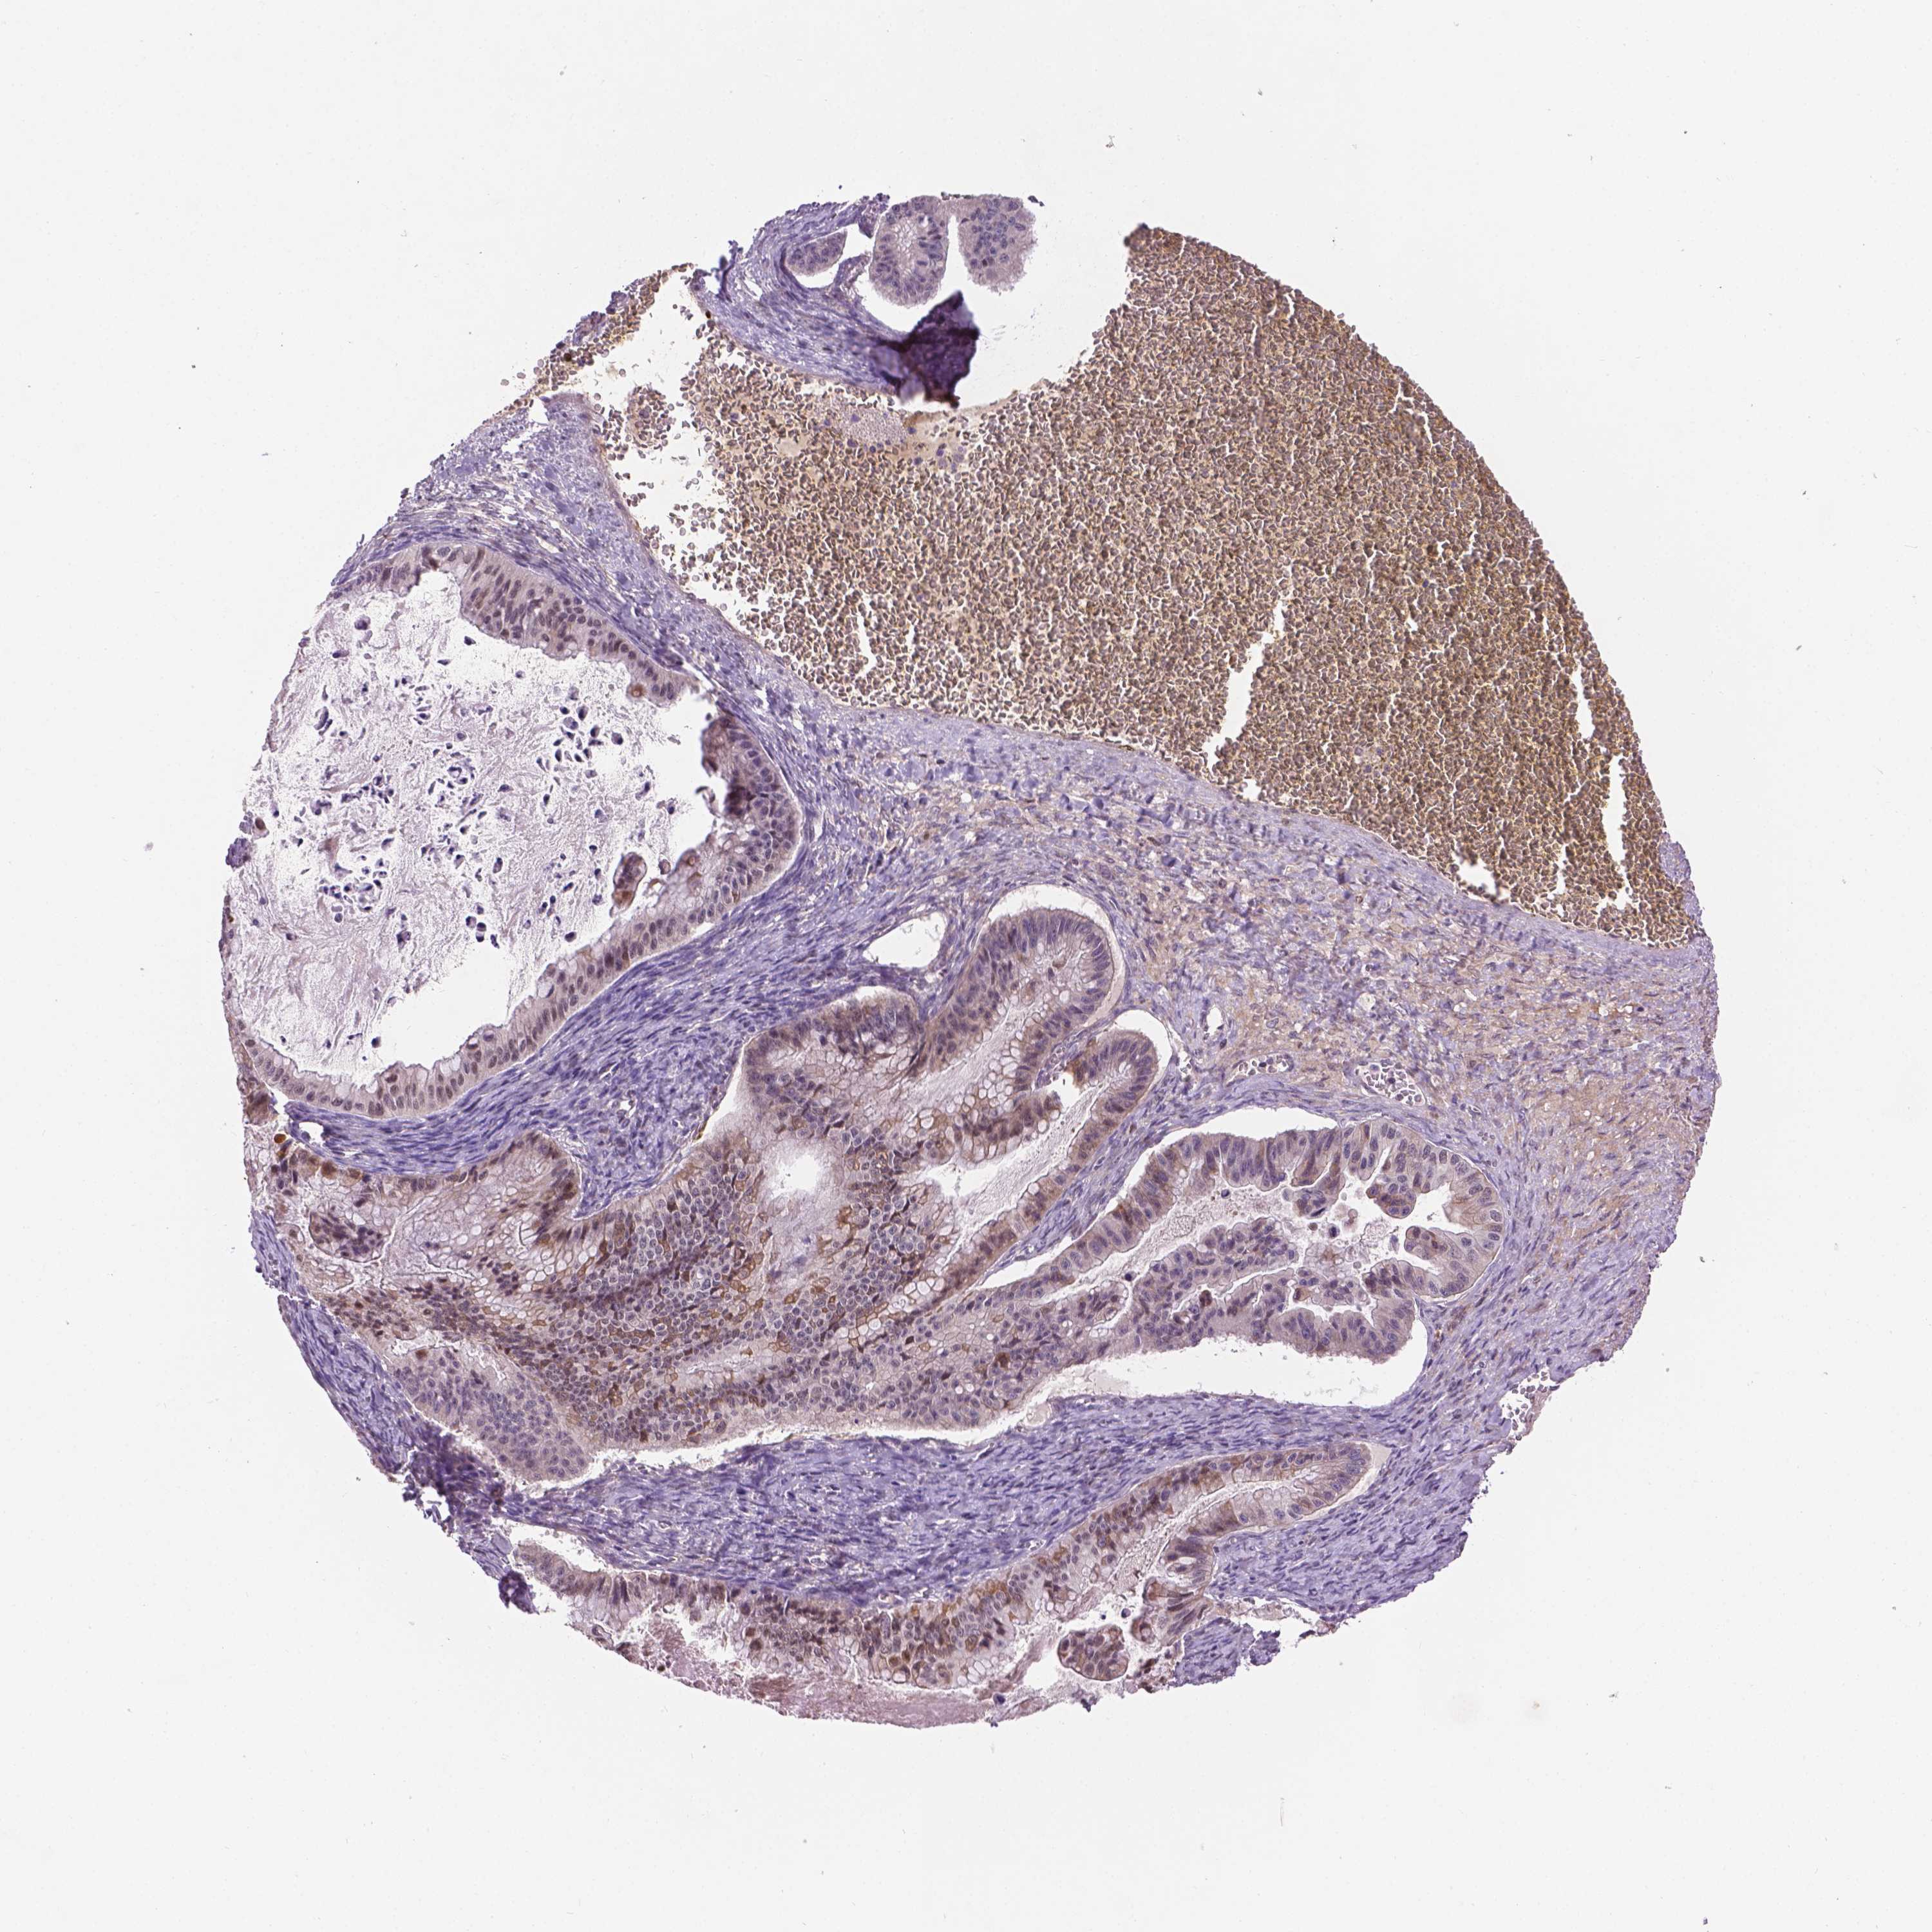

OVARIAN CANCER - Protein expressioni

A mouse-over function shows sample information and annotation data. Click on an image to view it in a full screen mode. Samples can be filtered based on level of antibody staining by selecting one or several of the following categories: high, medium, low and not detected. The assay and annotation is described here.

Note that samples used for immunohistochemistry by the Human Protein Atlas do not correspond to samples in the TCGA dataset.

Antibody stainingi

Antibody staining in the annotated cell types in the current human tissue is reported as not detected, low, medium, or high, based on conventional immunohistochemistry profiling in selected tissues. This score is based on the combination of the staining intensity and fraction of stained cells.

Each image is clickable and will lead to virtual microscopy that enables deeper exploration of all samples and also displays staining intensity scores, fraction scores and subcellular localization as well as patient and tissue information for each sample.

Antibody HPA063121

Staining

High

Medium

Low

Not detected

Intensity

Strong

Moderate

Weak

Negative

Quantity

>75%

75%-25%

<25%

None

Location

Nuclear

Cytoplasmic/membranous

Cytoplasmic/membranous,nuclear

Cystadenocarcinoma, serous, NOS

Cystadenocarcinoma, mucinous, NOS

Carcinoma, endometroid